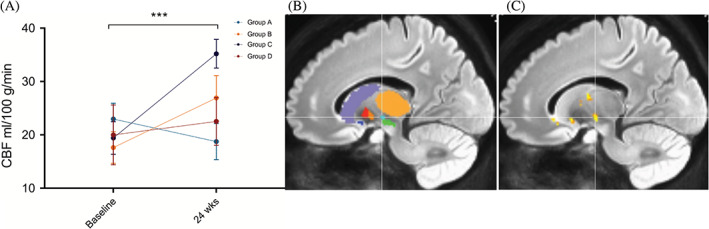

偽連續動脈旋轉顯示時間( P<0.001)和區域(P<0.001)的主效應顯著,但半球( P=0.401)或隊列(P=0.088)?的主效應不顯著。所有基底神經節結構的灌注從基線到輸注后24周總體增加。事后按區域時間比較顯示,同種異體hMSC輸注后,隨時間變化的灌注增加最顯著的是丘腦底核(圖2)。

方法:德克薩斯大學休斯頓健康科學中心神經內科在輕度至中度PD患者中進行了一項單中心、開放標簽、遞增劑量遞增的 1 期臨床研究。20名參與者依次進入4個劑量組中的1個并接受單次靜脈輸注:A組,1×106allo-hMSCs/kg;B組,3×106allo-hMSCs/kg;C組,6×106allo-hMSCs/kg;和D組,10×106allo-hMSCs/kg。受試者在輸注后第3、12、24 和52周返回進行評估。